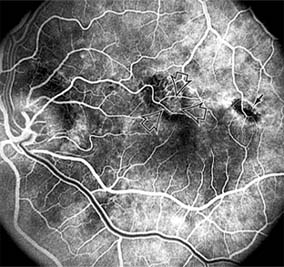

CENTRAL SEROUS CHORIORETINOPATHY

Central serous chorioretinopathy is characterized by serous detachment of the sensory retina as a consequence of focal leakage of fluid from the choriocapillaris through a defect in the retinal pigment epithelium (Figures 10-2 and 10-3). This disease typically affects young to middle-aged men and may be related to life stress events. Most patients present with the sudden onset of blurred vision, micropsia, metamorphopsia, and central scotoma. Visual acuity is often only moderately decreased and may be improved to near-normal with a small hyperopic correction.

Figure 10-3

Figure 10-3: Fluorescein angiogram of central serous chorioretinopathy shows active disease with both a retinal pigment epithelial detachment (small arrows) and a sensory retinal detachment (large arrows). Two foci of inactive disease (open arrows) are also present.

The diagnosis is made by slitlamp examination of the fundus; the presence of serous detachment of the sensory retina in the absence of ocular inflammation, subretinal neovascularization, an optic pit, or a choroidal tumor is diagnostic. The retinal pigment epithelial lesion appears as a small, round or oval, yellowish-gray spot that is variable in size and may be difficult to detect without the aid of fluorescein angiography. Fluorescein dye leaking from the choriocapillaris may accumulate below the pigment epithelium or sensory retina, resulting in a variety of patterns including the well-recognized smokestack configuration.